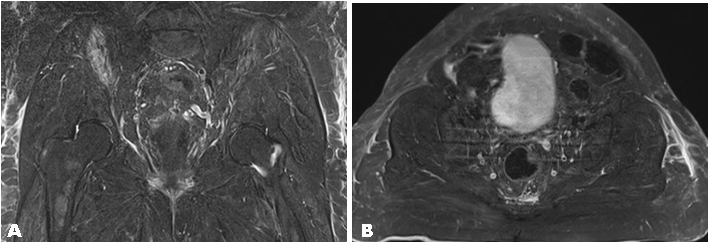

All identified Morel–Lavallée lesions were small (Figure 1) and (Figure 2). The right hip Morel–Lavallée lesion had a maximum width of 2.5 mm, and the left hip Morel–Lavallée lesion had a maximum width of 5 mm. Both collections above extend along the entire lateral aspect of the bilateral gluteus maximus. The third Morel–Lavallée lesion was superficial to the erector spinae muscles and extended from the level of the lumbosacral joint proximally with a maximum depth of 3.7 mm.

Figure 2: (A) Magnetic resonance imaging T2 turbo inversion recovery magnitude (TIRM) coronal cut, (B) Magnetic resonance imaging T2 turbo inversion recovery magnitude (TIRM) transverse cut.